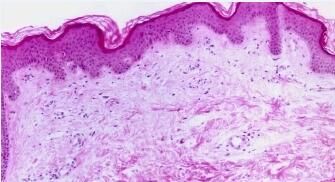

荨麻疹的危害有哪些吗?荨麻疹目前是一种过敏性皮肤病症,荨麻疹在发病时皮肤时常出现痒痛,随即产生风团,呈皮肤色,部分患者亦有水肿性红色斑点。有些人在感染荨麻疹后就擅自用一些抗过敏药物并没有引起重视,殊不知对病情变的越来越严重。那么,荨麻疹的危害有哪些吗?下面我们就听听京城专家为您讲解吧。

目前轻度荨麻疹者虽然没有太大的危害,但荨麻疹会有较剧烈的痒痛,从而严重影响了我们的生活和工作。但是荨麻疹如果反复出现很可能会逐渐转化成慢性荨麻疹,因此在荨麻疹初期发作的时候就一定尽快进行治疗,以免病情恶化。